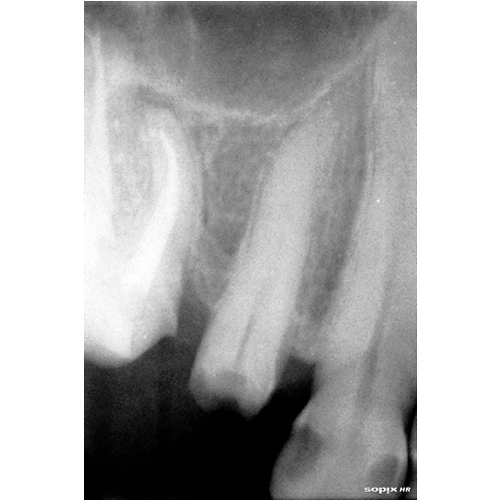

Nuestros procedimientos son realizados bajo magnificación microscópica